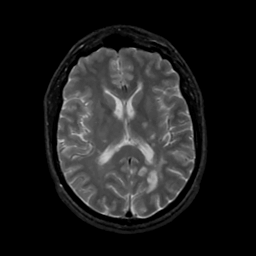

MR Study #8, March 31, 1991 -- Slice #28